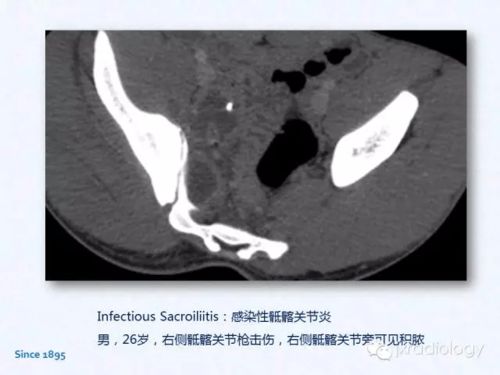

1. 更高的图像分辨率:CT可以提供横断面图像,图像分辨率高,可以清晰地显示组织结构和器官的细节,有助于更准确地诊断疾病。

9. 低对比度分辨率:CT对低对比度的组织结构(如软组织)的分辨能力较强,有助于发现微小病变。

CT扫描适用于各种疾病的诊断,如神经系统、心血管系统、呼吸系统、消化系统、泌尿系统等。在X光检查中,由于图像质量有限,一些疾病的诊断可能存在困难。而CT扫描可以提供更全面、准确的诊断信息。